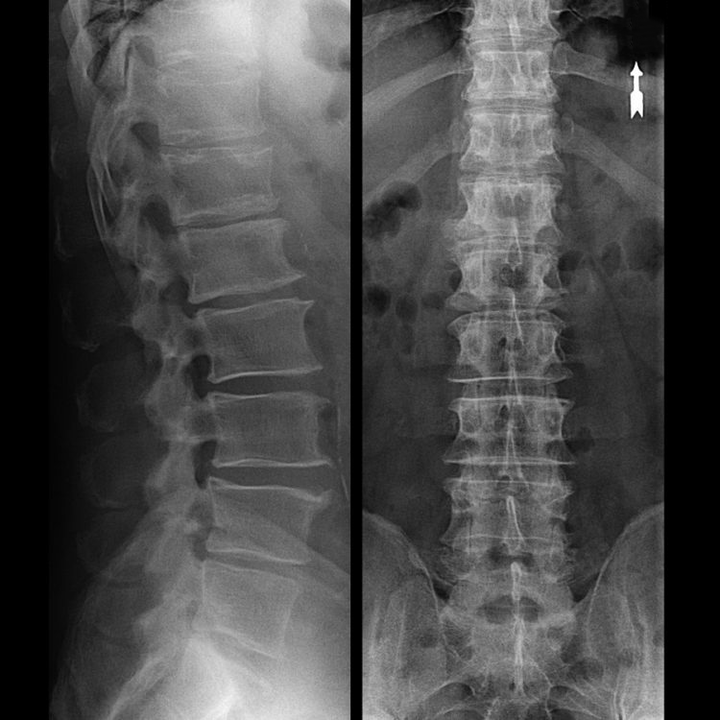

An “X-ray” of the cervical spine, and even with functional tests for flexion and extension, does not show cartilage, since their tissue transmits X-rays.Despite this, based on the location of the vertebrae, one can draw general conclusions about the height of the intervertebral discs, the general straightening of the physiological curvature of the neck - lordosis, as well as the presence of marginal growths on the vertebrae with prolonged irritation of their surfaces by fragile and dehydrated intervertebral discs.Functional tests can confirm the diagnosis of instability in the cervical spine.

Since the discs themselves can only be seen using CT or MRI, magnetic resonance and x-ray computed tomography are indicated to clarify the internal structure of cartilage and formations such as protrusions and hernias.Thus, with the help of these methods, a diagnosis is accurately made, and the tomography result is an indication, and even a topical guide, for the surgical treatment of a hernia in the neurosurgery department.

- You can regularly do at least an x-ray of the lumbar spine in two projections, or an MRI, to know whether the hernia, if any, is progressing;